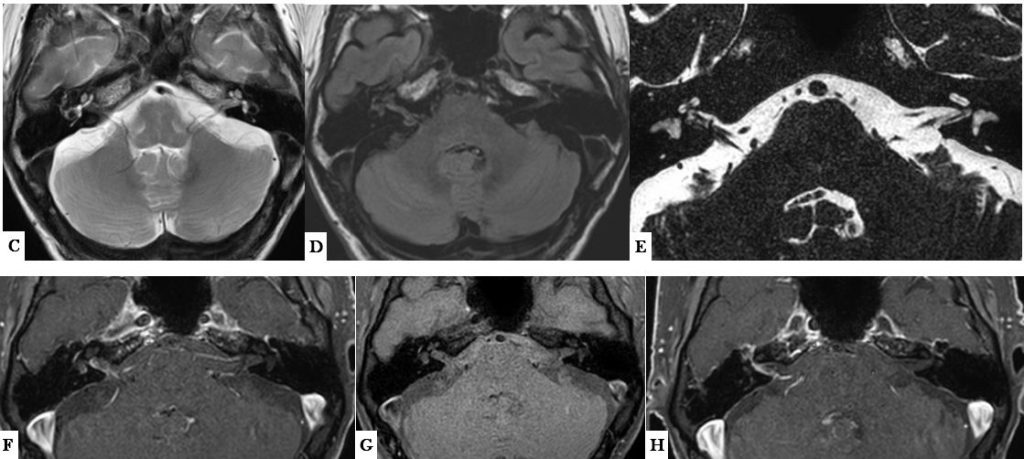

C. RM corte axial potenciado en T2. No alteraciones en la señal del tronco del encéfalo ni en el cerebelo. Ocupación discreta de la caja timpánica

D. RM corte axial portenciado en Flair. Hiperseñal en el conducto auditivo interno (CAI) y en el oído interno izquierdos con señal normal del lado izquierdo.

E. RM estudio 3DT2 –drive- con reconstrucción axial. Se identifican los nervios coclear y vestibular inferior en el CAI derecho, pero además existe un bucle vascular (se confirma rama de la AICA en el estudio angiográfico no mostrado) y una “estructura pseudolineal” que no permite definir bien el nervio vestibular.

F, G y H. RM cortes axiales T1 con saturación grasa, F y H tras administrar gadolinio. En el estudio sin gadolinio (G) existe una tenue hiperseñal de la cóclea y laberinto membranoso de forma comparativa con el lado izquierdo. Tras administrar gadolinio (F y H) existe refuerzo irregular de las paredes del CAI, segmento laberíntico y primera vuelta del nervio facial, y del vestíbulo derechos. Posible refuerzo asimétrico de la meninge derecha adyacente al borde posterior de la pirámide petrosa derecha.